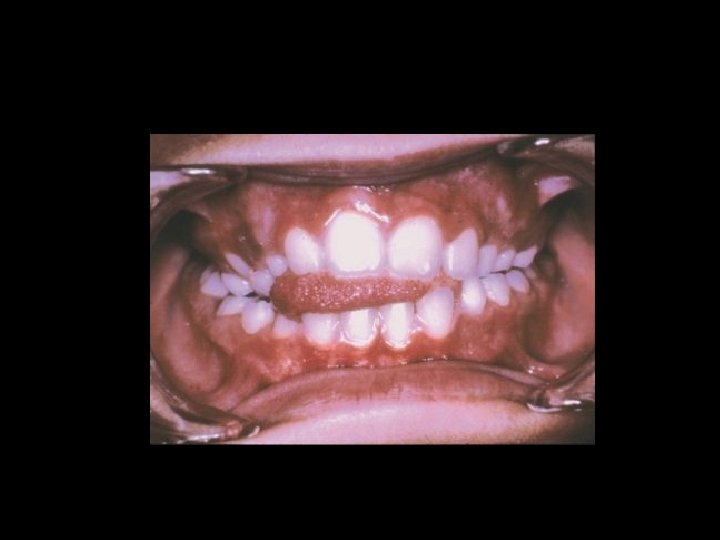

Il contenzioso PRINCIPALI AMBITI Ø Ø Ø La diagnosi La chirurgia orale La terapia conservativa Il trattamento delle anomalie dento-scheletriche La riabilitazione protesica

Responsabilità Ø Ø Ø Ø Garanzia di mezzi Garanzia di risultato Trattamento di soggetti in crescita Trattamento di soggetti al termine della crescita Comportamenti del paziente Risultato e recidiva Danni iatrogeni